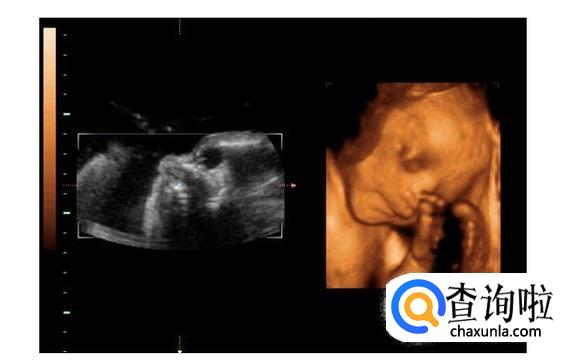

四维彩超是采用三维超声图像加上时间维度参数,可以更直观更清晰地呈现胎儿在宫内的动态图像,多方位、多角度地观察胎宝宝的生长发育情况。